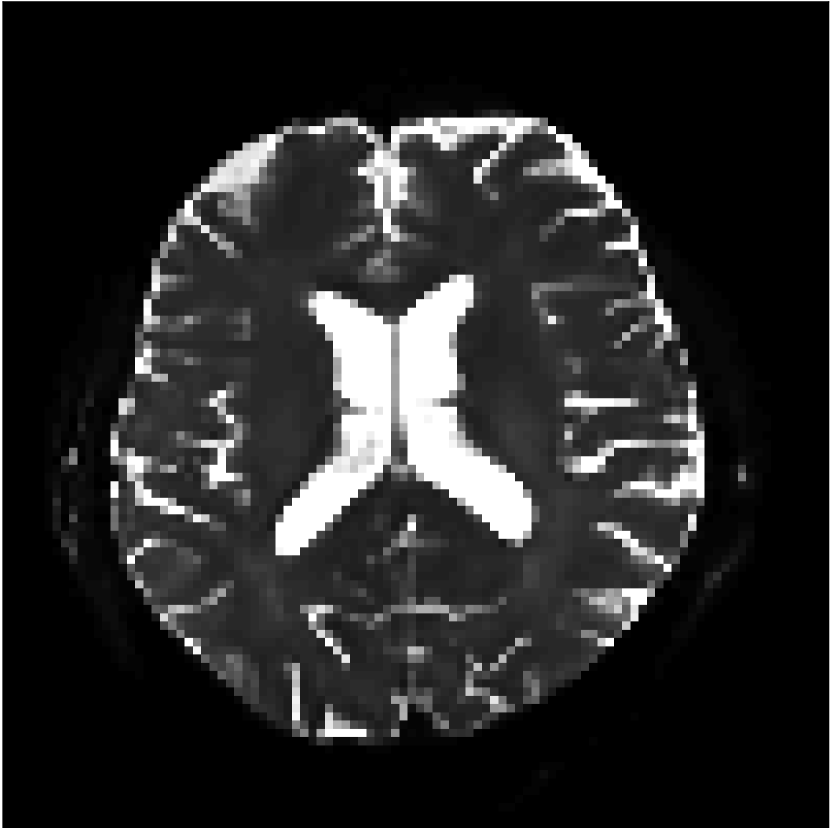

Figure 10 compares mean diffusivity maps across various partial Fourier factors between the CCNN and state-of-the-art methods.

No PF

7/8 PF

6/8 PF

5/8 PF

SoA

MD, m2/ms

CCNN

The methods perform similarly without partial Fourier acceleration, but as partial Fourier acceleration increases, the image is continually degraded in the SoA method, with "black voxels" appearing around the lateral ventricles. The CCNN method mitigates the appearance of these artifacts in the parameter maps.